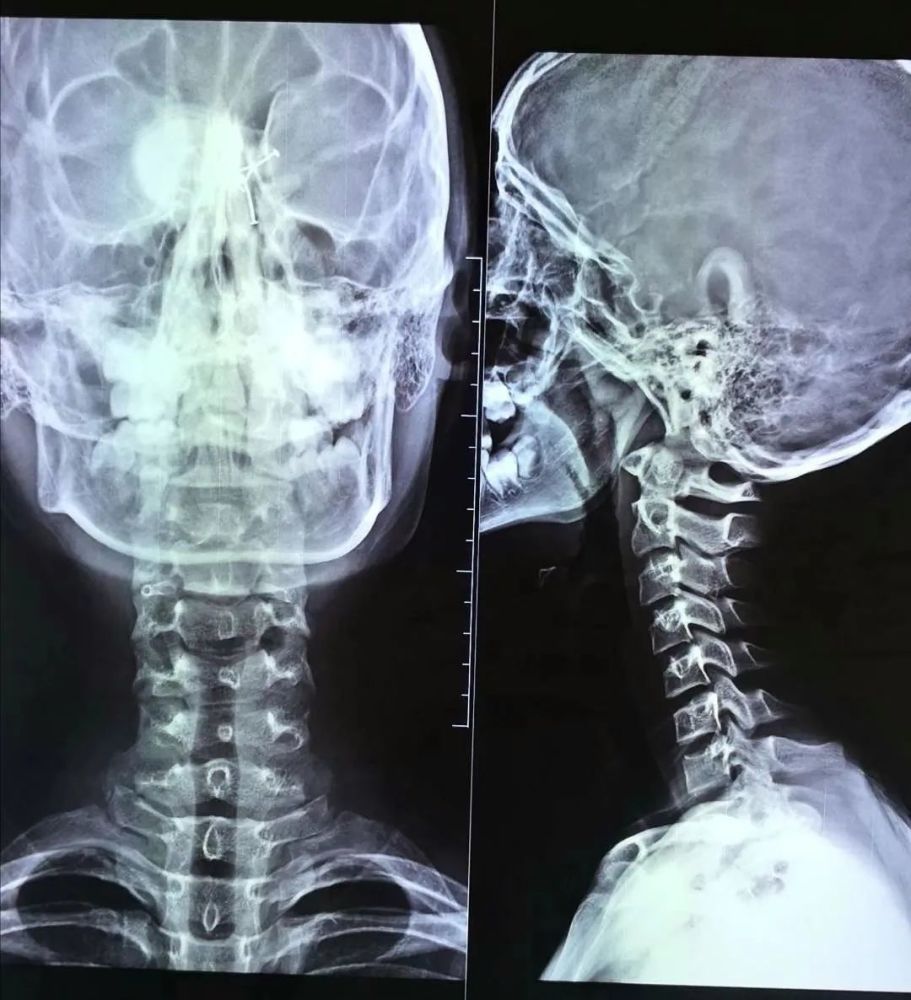

女子颈椎严重反曲畸形 湘雅专家助其脱离瘫痪危机

二,什么是颈椎生理曲度变直,反曲?

"颈椎反弓"即颈椎生理曲度反曲.

颈椎生理曲度反曲

也就是下面这张图所说的反曲,如果对顶角小于40°的话,表现颈椎的曲线